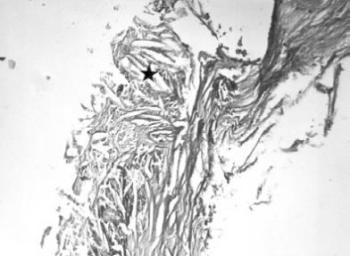

12. ábra. A 19. századi férfi múmia aortájában kifekélyesedett atheromás plakk, a koleszterin kristályok helyét tű alakú üregek (csillag) jelzik. HE festés 150× nagyítás